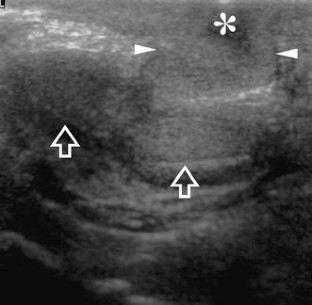

Fig. 3